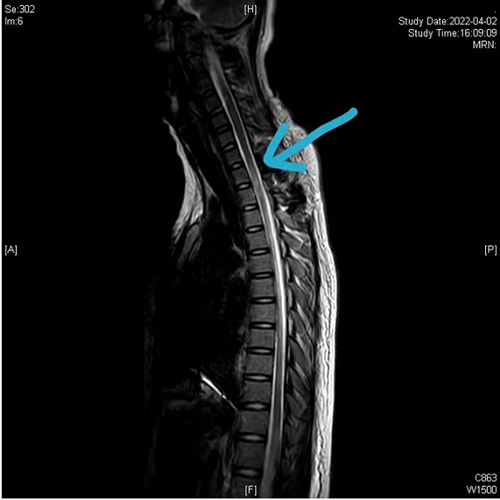

术后颈胸椎磁共振(蓝色箭头提示血肿已完全清除,脊髓通畅)